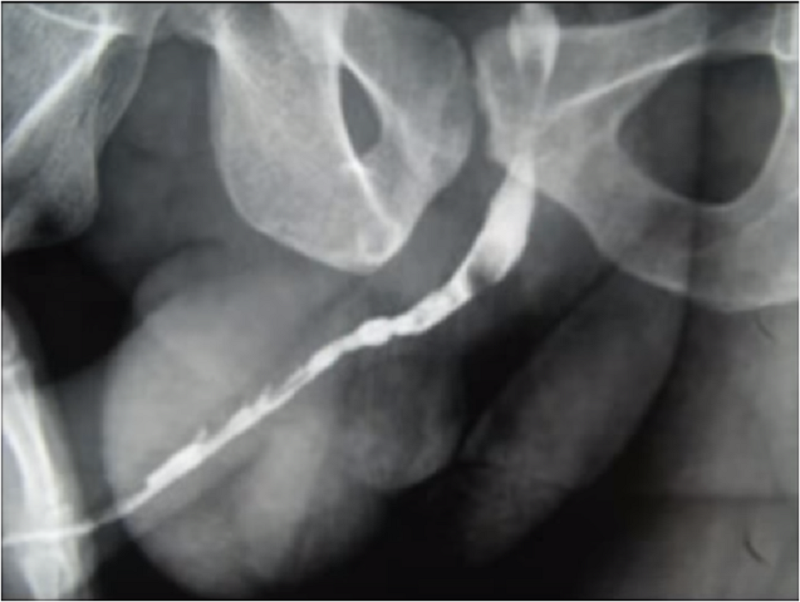

Слика 1. Стеснет мочен канал по целата должина (како изеден од молци). Резултат на тешки инфекции.